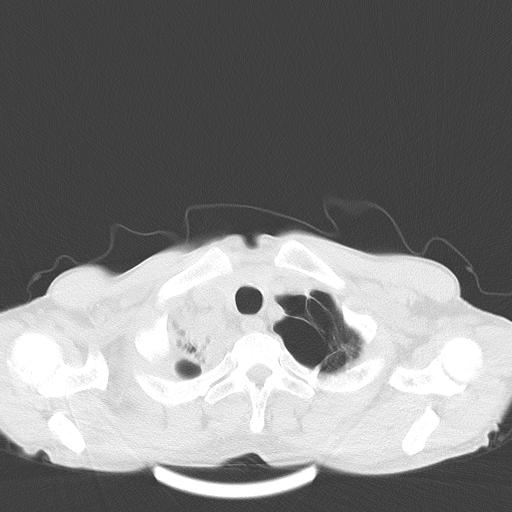

男性 75  咳嗽 一周前发热最高达39

右肺继发型tb并右侧tb性胸腔炎,右侧胸腔大量积液并右下肺膨胀不全,慢支肺气肿、多发肺大泡。建议抽胸水实验室检查并复查排除恶性在占位。

右上肺继发型肺结核,右胸腔中等量积液。

左上肺大泡。

结核的基础上有纵隔淋巴结肿大,右侧有胸水,但右侧纵隔反而窄,说明有肺有不张。

再就是右下肺有块影,和不张混合,还是不能除外肺癌。

补充材料,患者2月份ct片大致正常,双侧胸腔积液,2月份抽胸水未发现ca细胞,现患者发热,痰多,各气管通畅,

1)右肺继发型肺结核。2)左肺胸膜下多发性肺大泡。3)右侧胸腔积液。